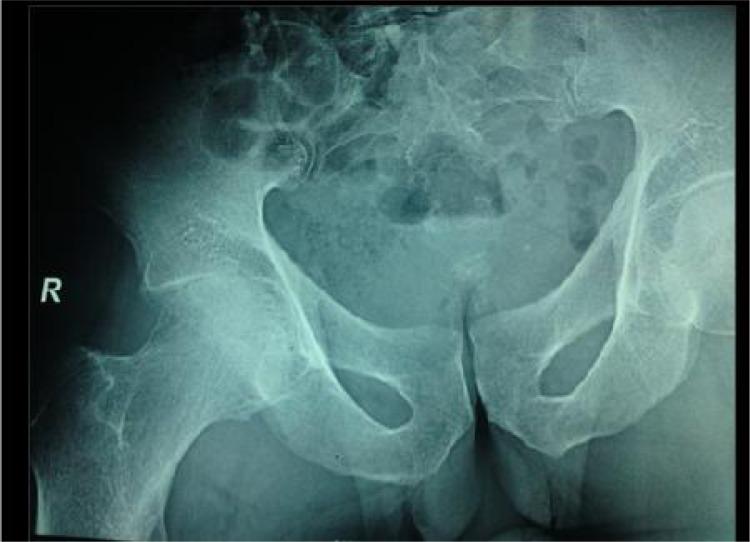

Brucellosis-induced avascular necrosis of the hip in a middle-aged person.

Femoral Head Avascular Necrosis Due to Brucella Infection: A Case Report.

Osteonecrosis of the femoral head due to brucellosis: a case report.

Brucellosis induced avascular necrosis of the femoral head in a 7 year old child.